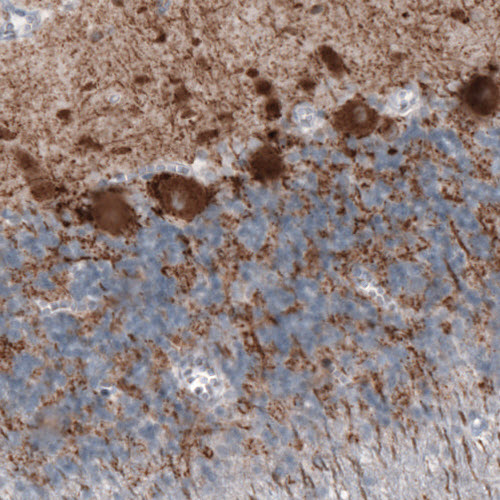

Immunohistochemical staining of rat globus pallidus shows strong immunoreactivity in GABAergic neural fibers.